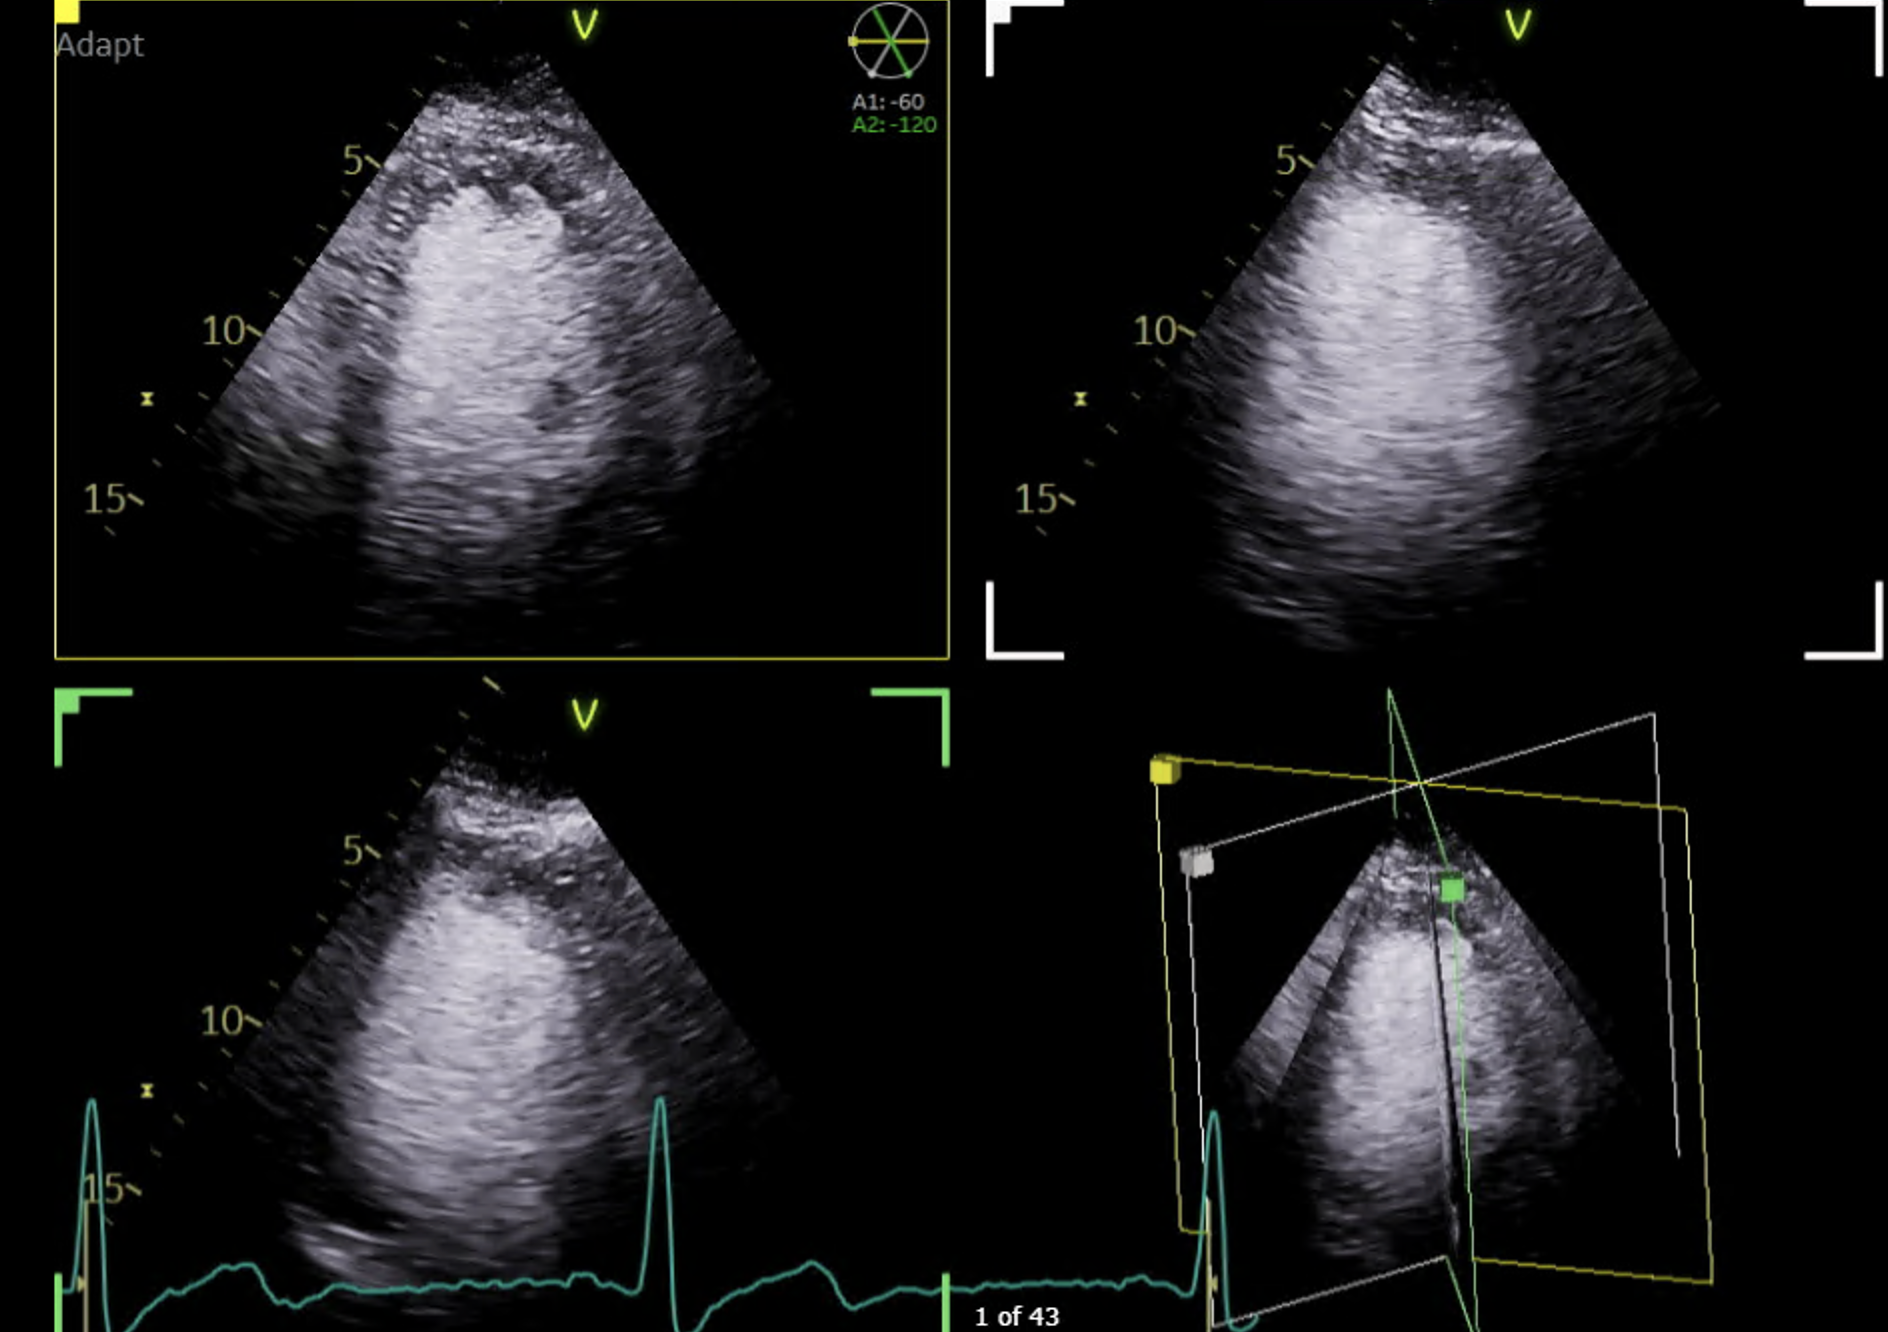

Transtoracic echocardiography (TTE) with contrast showing no residual LV thrombus, with 3D volume reconstruction.